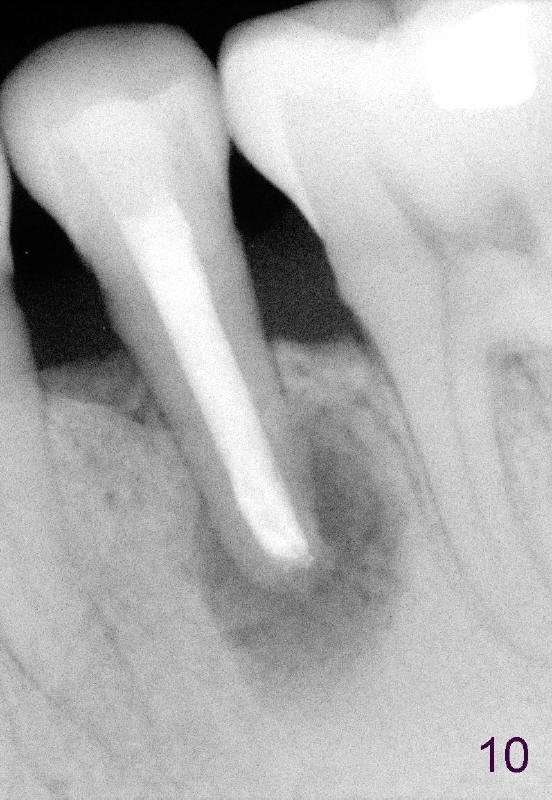

A 40-year-old Chinese man has periodic (once a month) mild pain and swelling in the lower left quadrant. Clinical exam reveals dens evaginatus (Fgi.1': <) in #20. Upon pressure from mouth mirror handle, there is limited amount of purulent discharge from the fistula (Fig.1": <). Preop PA shows a large canal with large periapical radiolucency (Fig.1). RCT started on Aug 6, 2010 with #70 file at 20 mm (Fig.2), #120 file at 16 mm (Fig.3) and CaOH paste in the canal (Fig.4). The dressing changed on Oct 8, 2010 (Fig.5). RCT finished on Jan 25, 2011 with master cone (rolled with several gutta perchae) (Fig.6), lateral condensation (Fig.7) and after vertical condensation and build-up (Fig.8). The canal was wet in the last two appointments with no sign of apexification. Follow up is done in 7 months (Fig.9), 11 months (Fig.10) and 18 months. Although the patient reports no pain after the treatment, the fistula remains with purulent discharge. The patient does not accept apical surgery. What should we do? Retreat with MTA (1,2,3)?